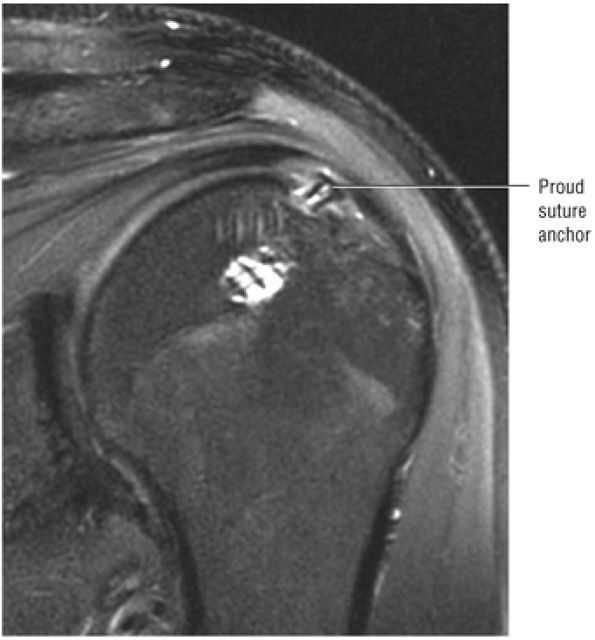

FIGURE 8.102 ● (A) The anterior undersurface of the acromion and the coracoacromial ligament form the coracoacromial arch. The subacromial subdeltoid bursa facilitates the passage of the rotator cuff and proximal humerus under the coracoacromial arch. (B) A superior axial image shows the anterior-to-posterior extent of the coracoacromial (CA) ligament perpendicular to the supraspinatus tendon. The fluid in the subacromial-subdeltoid bursa represents fluid between two serosal surfaces in contact with each other. One serosal surface is contributed by the undersurface of the coracoacromial arch and deltoid, and the other serosal surface is on the bursal side of the cuff.

|

![]() |